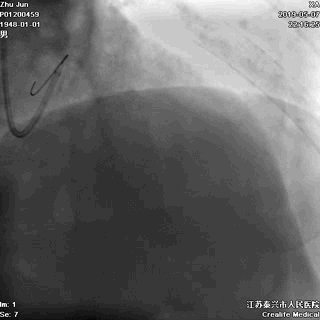

冠脉左主干线样狭窄

回旋支主支中段闭塞

前降支开口次全闭塞

导丝分别进回旋支和前降支